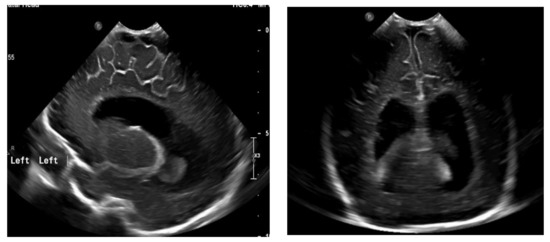

The next follow-up test, a fontanelle ultrasound, was performed every 5–7 days of neonatal life to assess the size of the cerebral ventricles and location of the posterior fossa structures. The dynamics of hydrocephalus progression was assessed based on the measurements of the lateral ventricular size (anterior horns and stem) and increased resistance index of the anterior cerebral artery (RI ACA) on follow-up ultrasound, as well as the measurements of the head circumference and palpable tension of the anterior fontanelle. The measurements were then used to determine the need to place Ventriculo-Peritoneal shunt (V-P-shunt) if the anterior horn and lateral ventricular size exceeded the 90th percentile on the pediatric ultrasound scale, and continued rising, RI ACA was >0.75, and increased tension of the anterior fontanelle failed to resolve [7,8] (Figure 3 and Figure 4).

Figure 3. Normal appearance and size of the ventricles on fontanelle ultrasound.

Figure 4. Ventriculomegaly, which requires V-P shunting on fontanelle ultrasound.